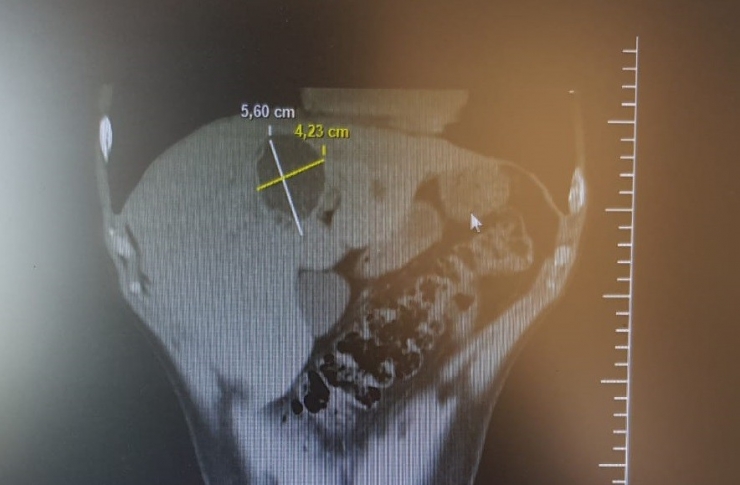

Bilecik Devlet Hastanesinde tedavi altında bulunan Sadık Akşehir (40) hasta karaciğer kist hidatik (hayvan kisti) kapalı kist ameliyatı (laparoskopik kistektomi) oldu. 5,60 ile 4,23 santimetre çapındaki kist 3 saatlik bir ameliyatın ardından alınarak, hasta 3 gün taburcu edildi. Hasta eski sağlığına kavuşurken, ameliyatı yapan Genel Cerrah Uzmanı Op. Dr. Süleyman Deniz Kahraman'a teşekkür etti.